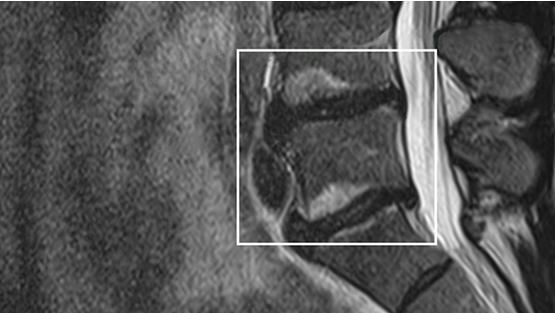

MRI scan highlighting vertebral endplates.

Photograph by Boston Scientific

MRI image showing Modic changes

For many years, there wasn’t a treatment for people whose MRIs showed Modic changes. For this reason, Modic changes can sometimes be overlooked on an MRI. Modic changes are now recognized as a clear and objective sign of vertebrogenic pain. It’s important to ask your doctor to look closely at your MRI for Modic changes.